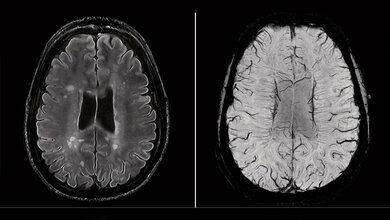

Für die Studie hat ein Team des Arbeitsbereichs Biologische Psychologie und Neuropsychologie in Kooperation mit dem LV Prasad Eye Institute in Hyderabad (Indien) Menschen untersucht, die aufgrund von beidseitigem Grauen Star teilweise mehrere Jahre nach der Geburt blind waren und deren Augenlicht dann durch eine Operation wiederhergestellt werden konnte. Von allen Teilnehmenden, die zum Zeitpunkt der Studie zwischen sechs und 36 Jahren alt waren, wurden mit Hilfe eines Kernspintomographen Bilder des Gehirns aufgenommen, aus denen anschließend für jede Person ein 3D-Modell des Gehirns rekonstruiert wurde. In diesem Modell konnten die Forschenden messen, wie dick und wie groß die Oberfläche der Hirnrinde in den visuellen Arealen des Gehirns war.

Die Hirnrinde ist die äußerste, mehrfach gefaltete Schicht des Gehirns, die mehrere Millimeter dick ist und hauptsächlich aus Zellkörpern von Nervenzellen besteht, der so genannten grauen Substanz. Durch ihre mehrfache Faltung besitzt die Hirnrinde eine große Oberfläche und bietet viel Platz für Milliarden von Nervenzellkörpern, die für die Verarbeitung sensorischer Information und damit für die Entstehung von Wahrnehmung zuständig sind. In der normalen Entwicklung wird die Hirnrinde ab einem Alter von ein bis zwei Jahren dünner, während ihre Oberfläche bis in die Pubertät zunimmt. Beide strukturellen Veränderungen sind wichtig für die vollständige Reifung neuronaler Netzwerke.

Das Forschungsteam fand heraus, dass bei den vormals blinden Menschen die Sehrinde, also der Teil der Hirnrinde, in dem die Sehinformation verarbeitet wird, sowohl eine kleinere Oberfläche besaß als auch dicker war. Ihre Sehrinde ähnelte mehr der von Menschen, die seit ihrer Geburt dauerhaft blind waren als der von Menschen, die von Geburt an sehen konnten. Außerdem sagte das Ausmaß der Veränderungen in der Sehrinde vorher, wie gut die Menschen nach der Entfernung des Grauen Stars sehen lernten.